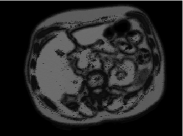

We used whole body PET-CT scans of 10 female and 10 male patients. The voxel size of the CT images is 1.17 mm x 1.17 mm x 1.17 mm (interpolated from 5 mm slices). We focus on the abdominal region and have selected the following five objects from each subject: skin boundary, liver, left kidney, right kidney and spleen.

We use leave-one-out-cross-validation (LOOCV) to measure recognition performance for each subject type. Translation, scale, and orientation components of the relationship function are evaluated separately. The range of scale component in LOOCV tests was found to be . Figures 5 and 6 show recognition accuracy in terms of mean translation error over all objects for female and male subjects, respectively, and the different combinations of objects included in the model assembly (shown along the horizontal axis). All results displayed are for coarse recognition only. As easily noticed, the minimum mean translation errors are obtained when all the objects are included in the recognition process. Different combination of objects yields different results. Size and spatial position of the objects play an important role in recognition: it is easier to recognise large objects than smaller objects. Similarly, Figures 7 and 8 show recognition accuracy in terms of mean orientation error (in degrees) for female and male data, respectively. Note that the minimum mean orientation error is obtained when all the objects are included in the recognition process.

We observe that the effectiveness of object recognition depends on the number and distribution of objects considered in . Recognition accuracy is improved with the increasing number of objects. The evaluated results indicate: (1) High recognition accuracy can be achieved by including a large number of objects which are spread out in the body region. (2) Incorporating local object scale information improves the recognition in a way that there is usually no need to do search for scaling, orientation, and translation parameters. (3) The appearance information incorporated via b-scale has strong effect on the computation of PC system, and on the relationship function .